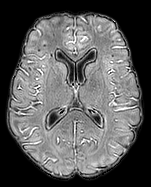

The detection of new multiple sclerosis (MS) lesions is an important marker of the evolution of the disease. The applicability of learning-based methods could automate this task efficiently. However, the lack of annotated longitudinal data with new-appearing lesions is a limiting factor for the training of robust and generalizing models. In this work, we describe a deep-learning-based pipeline addressing the challenging task of detecting and segmenting new MS lesions. First, we propose to use transfer-learning from a model trained on a segmentation task using single time-points. Therefore, we exploit knowledge from an easier task and for which more annotated datasets are available. Second, we propose a data synthesis strategy to generate realistic longitudinal time-points with new lesions using single time-point scans. In this way, we pretrain our detection model on large synthetic annotated datasets. Finally, we use a data-augmentation technique designed to simulate data diversity in MRI. By doing that, we increase the size of the available small annotated longitudinal datasets. Our ablation study showed that each contribution lead to an enhancement of the segmentation accuracy. Using the proposed pipeline, we obtained the best score for the segmentation and the detection of new MS lesions in the MSSEG2 MICCAI challenge.